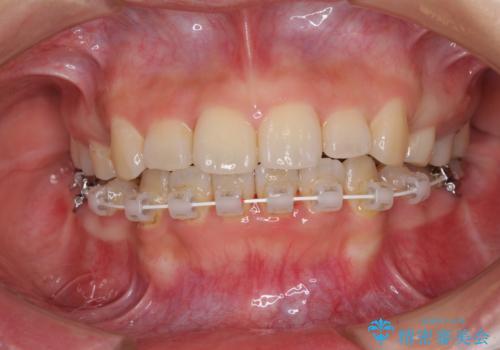

デコボコと膨らんだ口元 ハーフリンガルによる抜歯矯正とインプラント補綴治療

- 前歯のデコボコと上顎の前突感による口の閉じにくさを気にして来院された患者様です。

目立たない装置を希望されたので、上顎が裏側装置のハーフリンガルを選択し、上下左右の小臼歯(計4歯)を抜歯して矯正治療を行うこととしました。

デコボコの解消までは非常にスムーズでしたが、咬合力が強いためか、スペースを閉じるまでに長い期間を要しました。